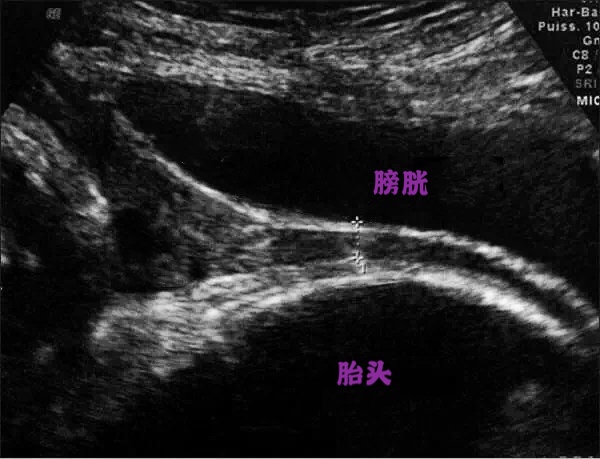

4、中晚孕期疑前壁胎盘粘连孕妇

中晚孕时特别是第一胎有剖宫产的孕妇,需要通过超声来观察胎盘粘连及其分度,中晚孕的孕妇因为有胎儿对膀胱的压迫,孕妇常会感到尿频导致更不能憋尿过多,怀疑胎盘粘连的孕妇只需要有憋尿的感觉即可,喝250ml温开水后半小时可检查。